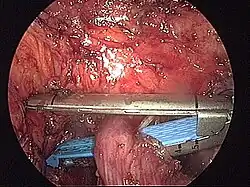

- Schematyczne obrazy jelita grubego i uchyłków esicy i śródoperacyjne obrazy uchyłków i nowotworu jelita grubego

Śródoperacyjny widok uchyłków esicy (operacja laparoskopowa).

Śródoperacyjny widok nowotworu esicy (operacja laparoskopowa).